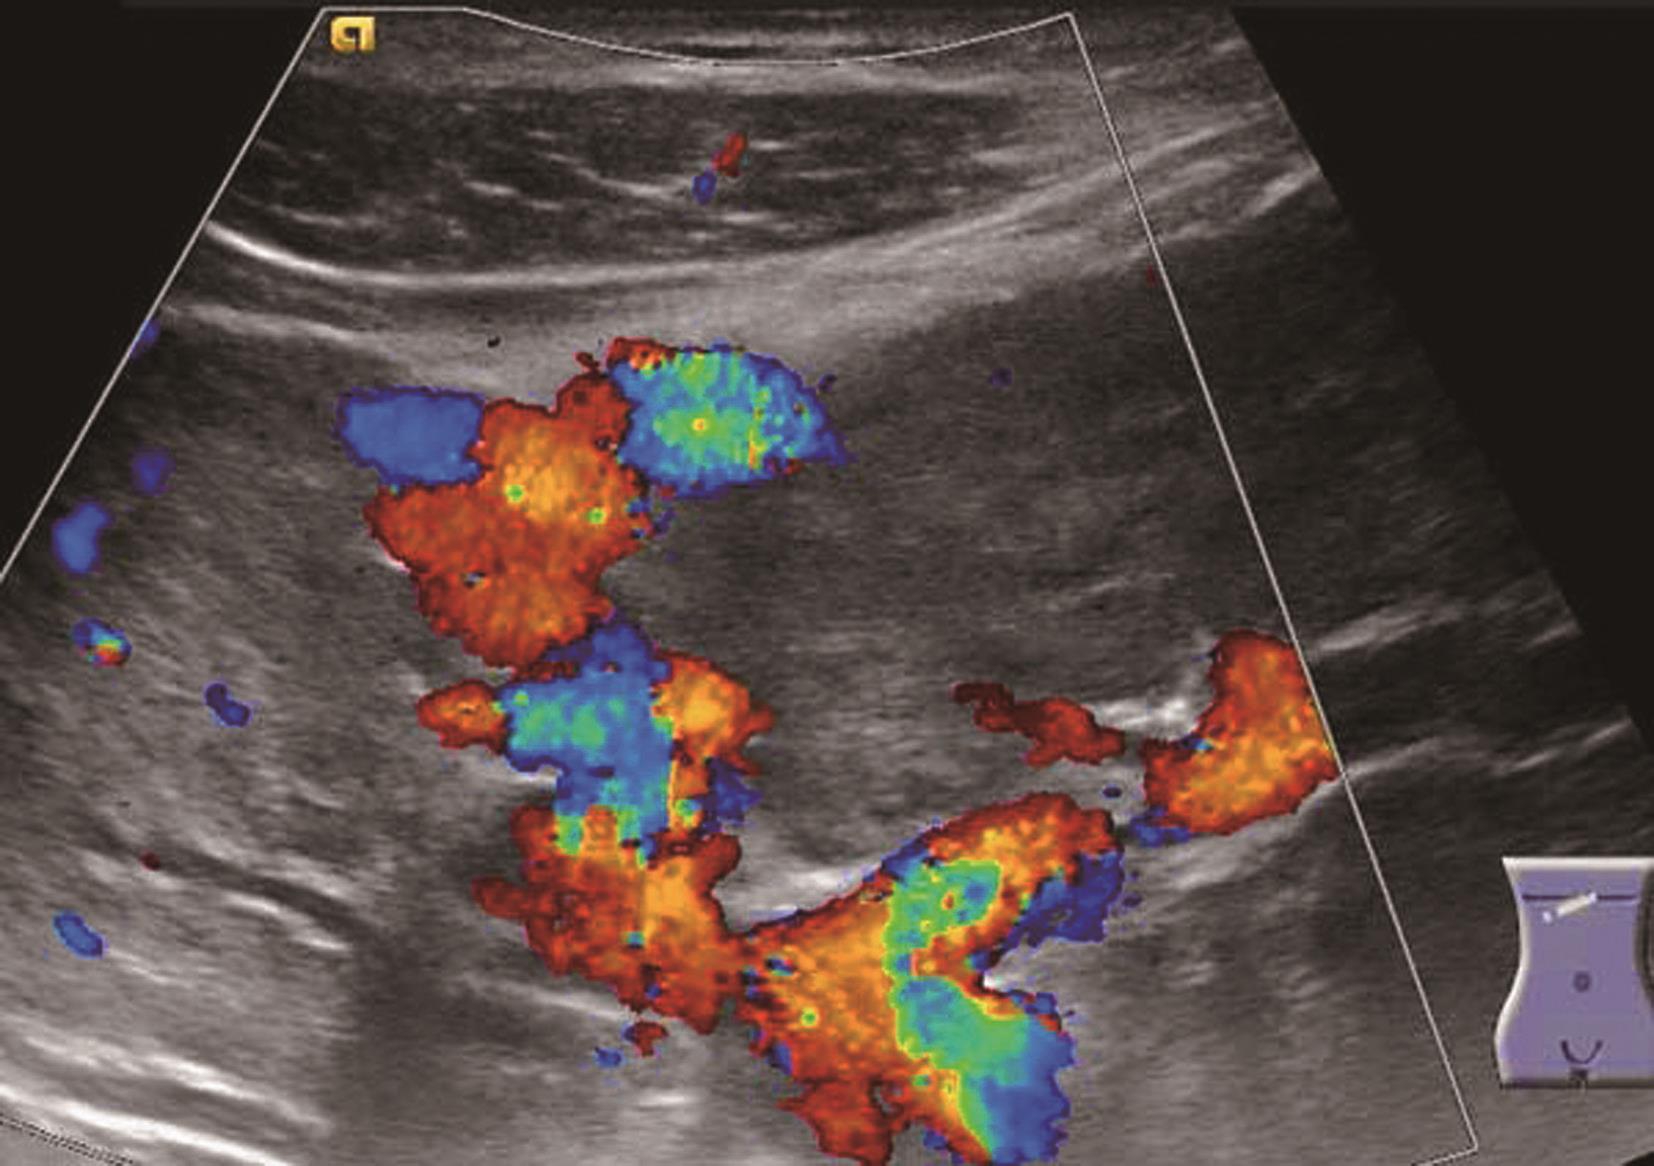

(2)彩色多普勒血流成像:又称彩色多普勒超声,以红、蓝、绿三基色及三基色混合产生的二次色显示人体组织器官及病灶内的血流信息。通常人为设定红色表示血流朝向探头,蓝色表示血流背离探头。色彩的灰度显示速度的大小,越亮表示血流速度越快,色彩越暗表示血流速度越慢。应用彩色多普勒技术可以检出人体组织器官及病灶内的血流信息,鉴别脏器内管道的性质,判断动脉或静脉,显示血管的起源、走向、时相和管腔内血流的性质,观察血管有无狭窄、梗阻、扭曲或动静脉畸形和心腔内异常通道形成,引导频谱多普勒取样位置的放置。根据肿瘤内部血管的分布、血管数目的多少可用以鉴别肿瘤的良恶性。通常瘤体血供越丰富,其恶性程度越高。

(2)彩色多普勒超声:

显示病变内外血供较丰富,可见一粗大的动脉血流伸入病灶中央并形成放射状或轮辐状排列,脉冲多普勒为低阻动脉血流频谱。具体如图5-21-16所示。

图5-21-16 肝脏局灶性结节增生彩色多普勒图像